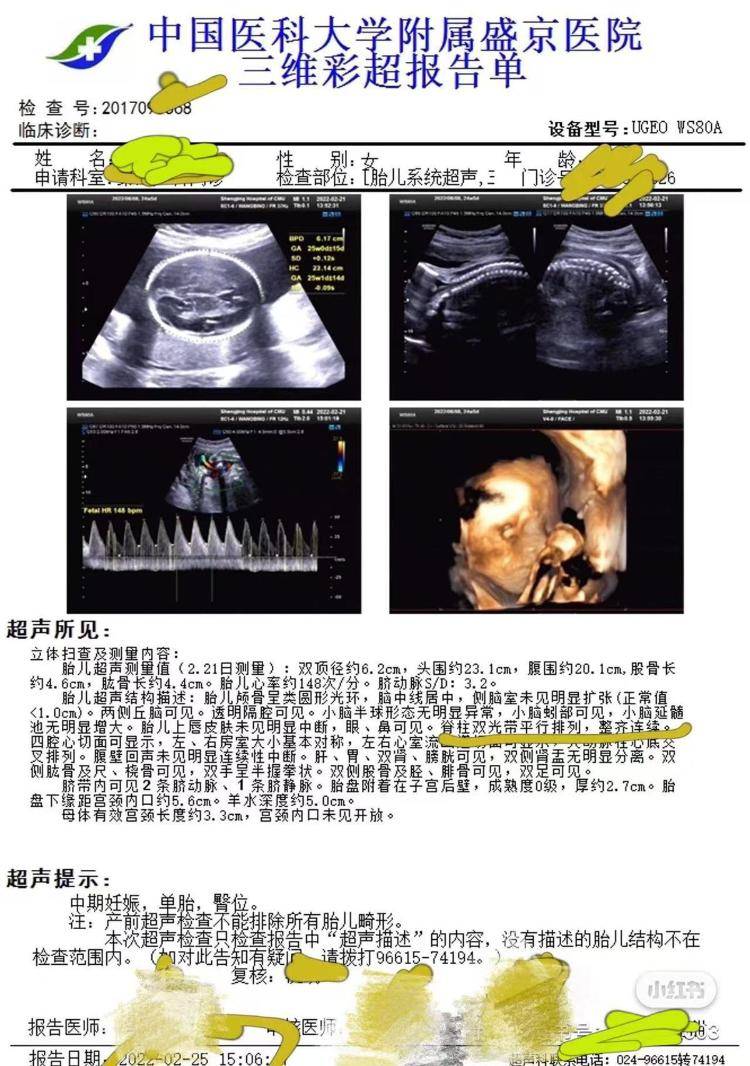

3月11日,高女士告诉极目新闻记者,2021年10月,她到盛京医院做了第一次产检并预约了后续的检查,2022年2月25日,她在盛京医院做了包括胎儿系统超声在内的大排畸检查,检查结果显示胎儿“脊柱双光带平行排列,整齐连续”,2022年6月15日,女儿出生理财的利率。同年12月,女儿在核磁检查时被确诊脂肪脊髓脊膜膨出和椎管内脂肪瘤,即“脊柱裂”,“脊柱裂意味着女儿后期需要多次手术治疗,否则会足踝畸形、大小便失禁,严重的话甚至会导致下半身瘫痪。”

产前彩超显示胎儿脊柱正常(受访者供图)